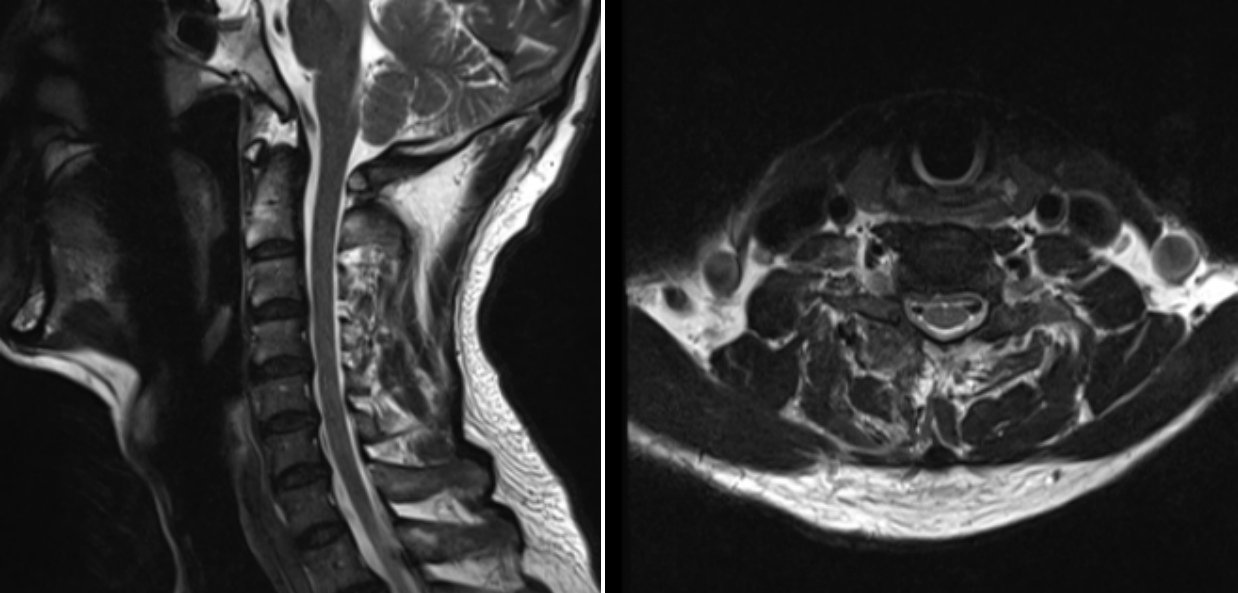

術(shù)后第一天MRI圖像

術(shù)后效果立竿見影,患者的疼痛癥狀得到了顯著緩解,麻木感也逐漸消退。術(shù)后1天,患者便能在醫(yī)護(hù)人員的指導(dǎo)下下床活動。經(jīng)過3天的觀察與護(hù)理,患者身體狀況良好,順利出院,手術(shù)取得圓滿成功。